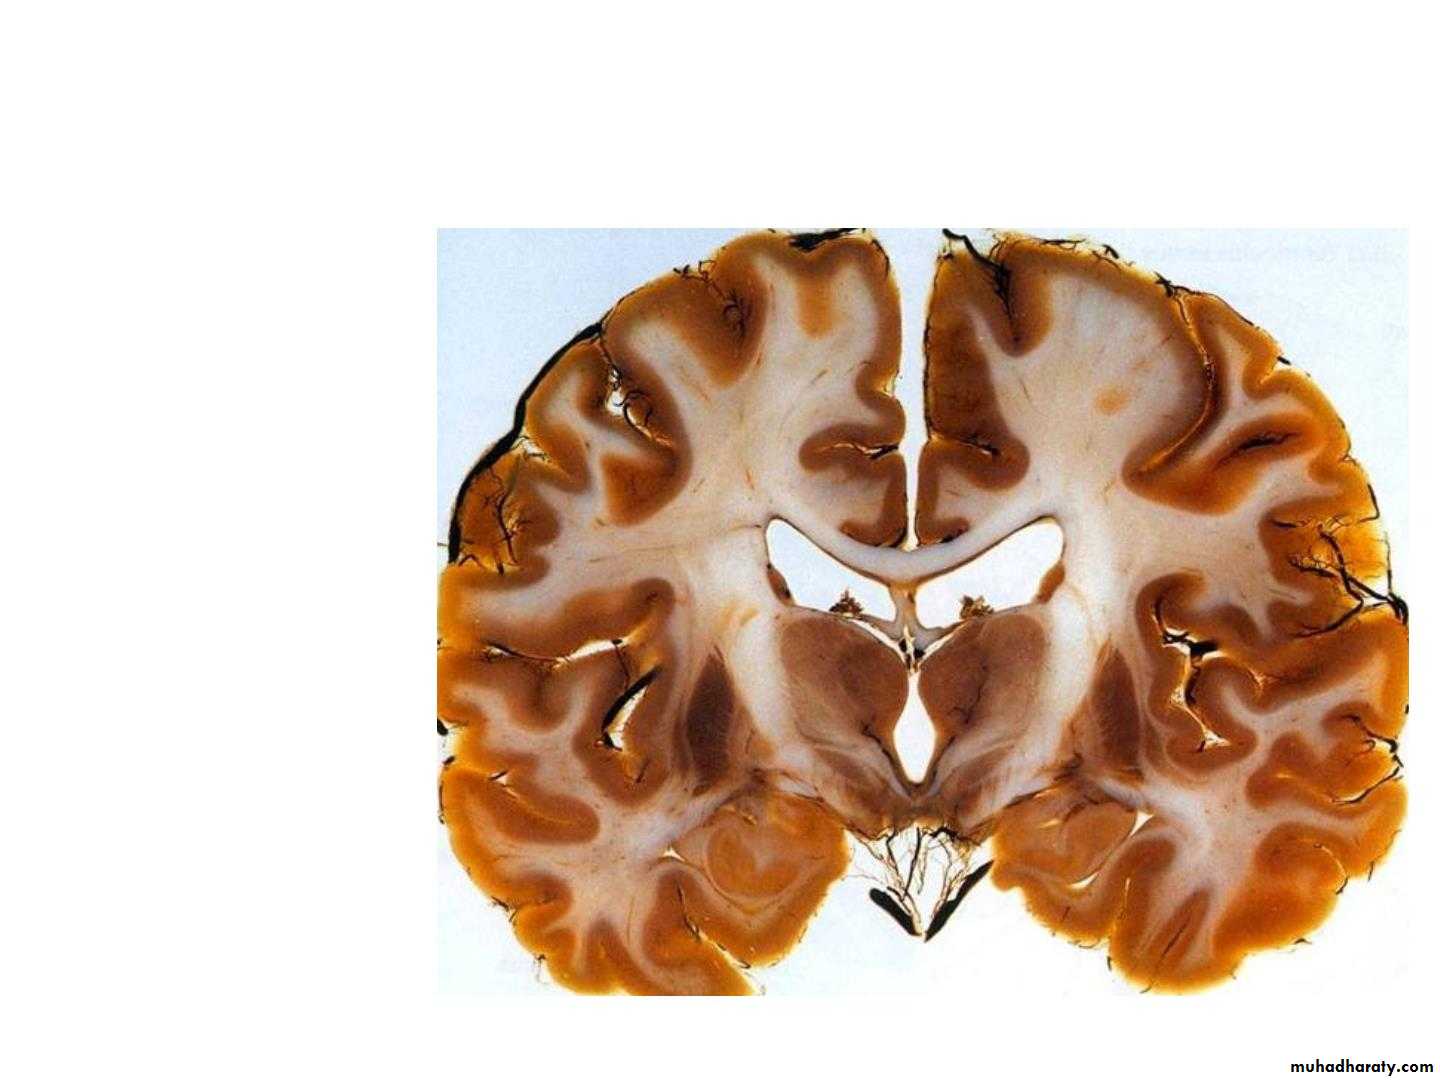

• Site:- It is the part of the forebrain which lies above the• midbrain, between the lower parts of the 2 cerebral

• hemispheres.

• • It consists of:

• 1. Thalamus:-the large oval mass of grey matter

• 2. Subthalamus:- it lies directly above midbrain

• 3. Hypothalamus: lies infront of subthalamus

• 4. Metathalamus: formed by lateral & medial geniculate

• body

• 5. Epithalamus: Formed of pineal body, 2 habenular

• nuclei & posterior commissure.

• The third ventricle lies between the 2 halves of the

• diencephalon.